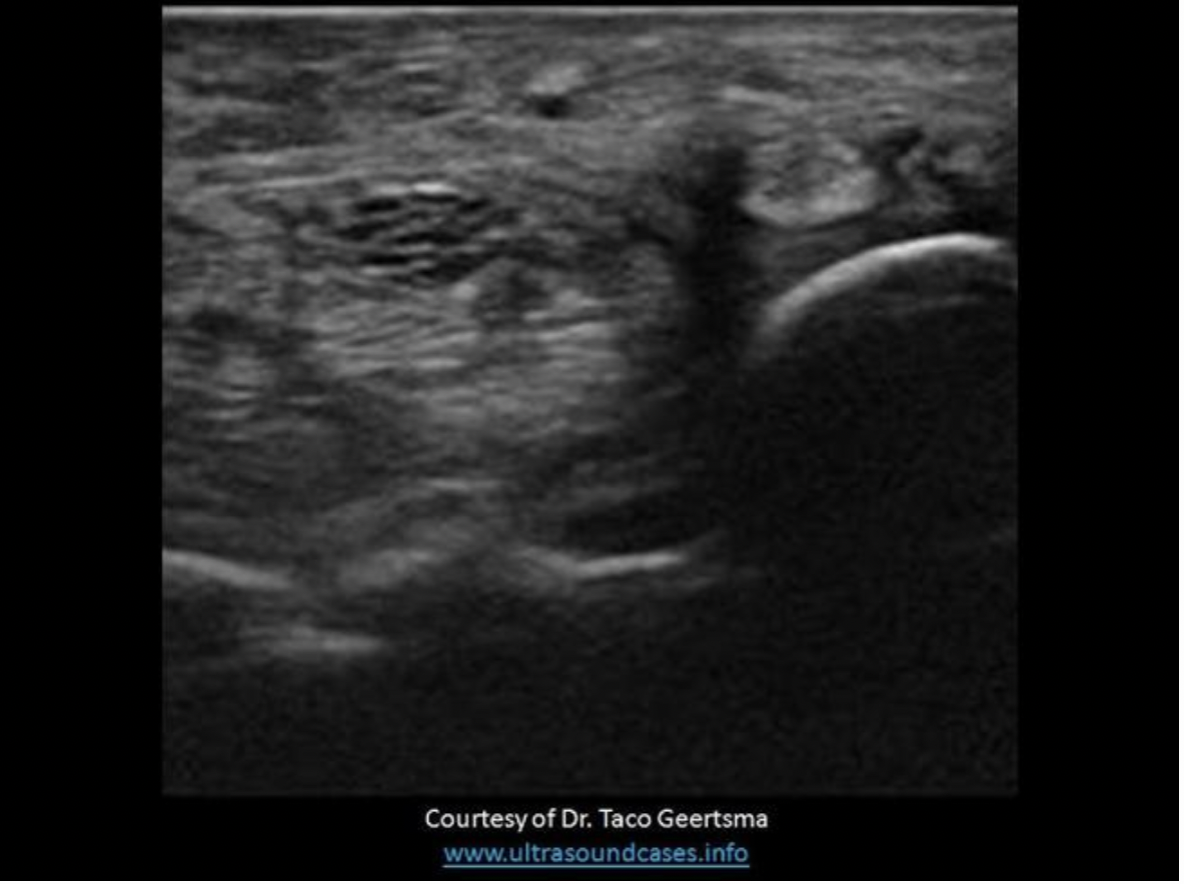

On an ultrasound exam, the normal adrenal cortex appears:

C. as a hypochoic ring around the echogenic medulla